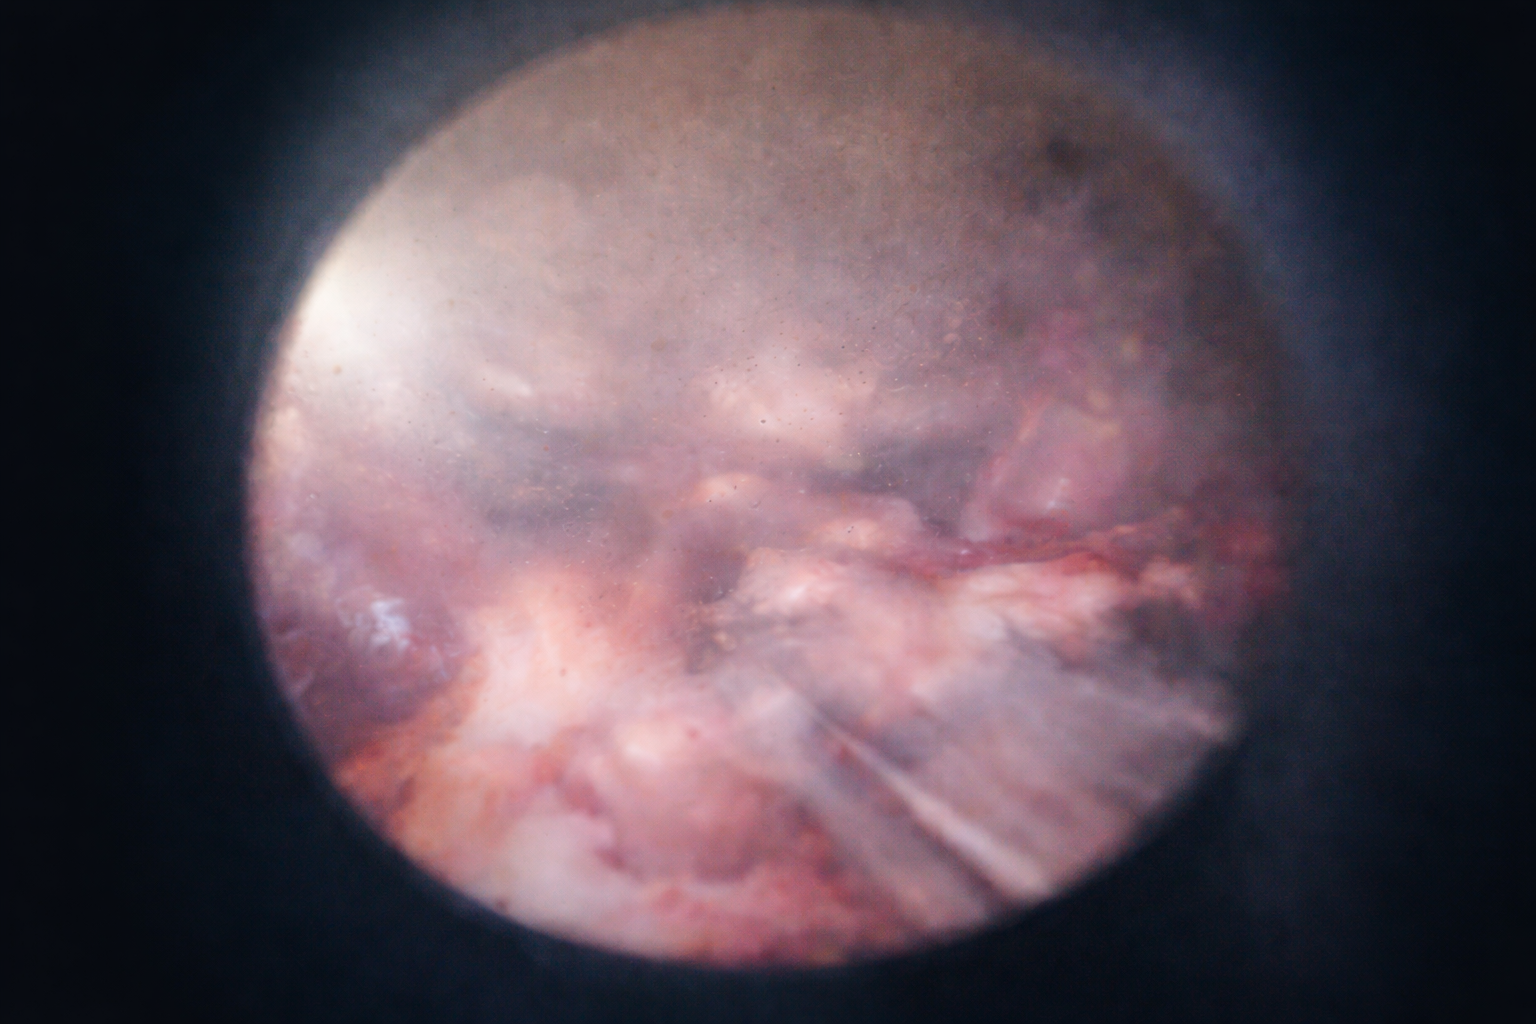

Hydrodissection + suction/irrigation for a clear, controlled field

Fine-tip hydrodissection creates natural planes + improves visualization